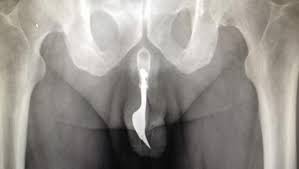

El anciano acudió al hospital con el pene sangrando. Al realizarle una radiografía, los médicos no podían salir de su asombro al descubrir un tenedor de 10 centímetros dentro de su uretra.

Al parecer, el hombre comenzó clavándose el utensilio porque le daba placer, cuando el juego sexual se le fue de las manos y el tenedor acabó totalmente atascado dentro de la uretra, tal y como se puede ver perfectamente en la radiografía.